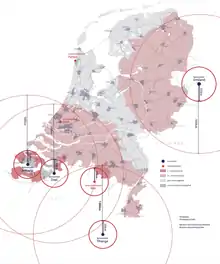

The Netherlands

In the Netherlands, the central storage of iodine-pills is located in Zoetermeer, near The Hague. In 2017, the Dutch government distributed pills to hundreds of thousands of residents who lived within a certain distance of nuclear power plants and met some other criteria.[49][50]